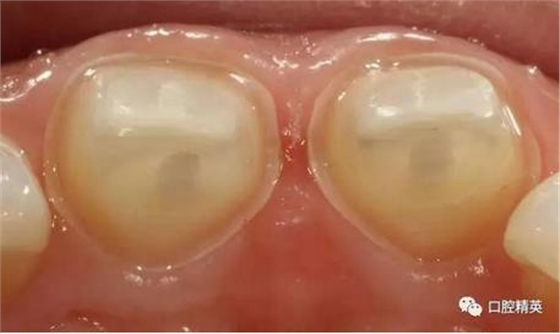

檢查:11,21近中鄰面可見(jiàn)樹(shù)脂類充填體,兩牙唇側(cè)根尖部有膿包狀突起,觸診疼痛,11,21無(wú)松動(dòng),叩診稍有不適,冷熱診檢查無(wú)反應(yīng),X-ray示11,21充填體底部近髓,根尖區(qū)無(wú)明顯異常影像。

術(shù)前檢查

可見(jiàn)兩側(cè)齦緣外形不平整

齲洞低已近髓